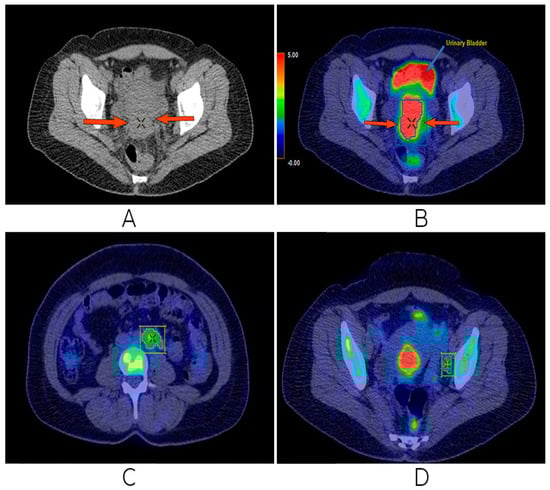

2.2. Imaging, Treatment Strategies, and Response